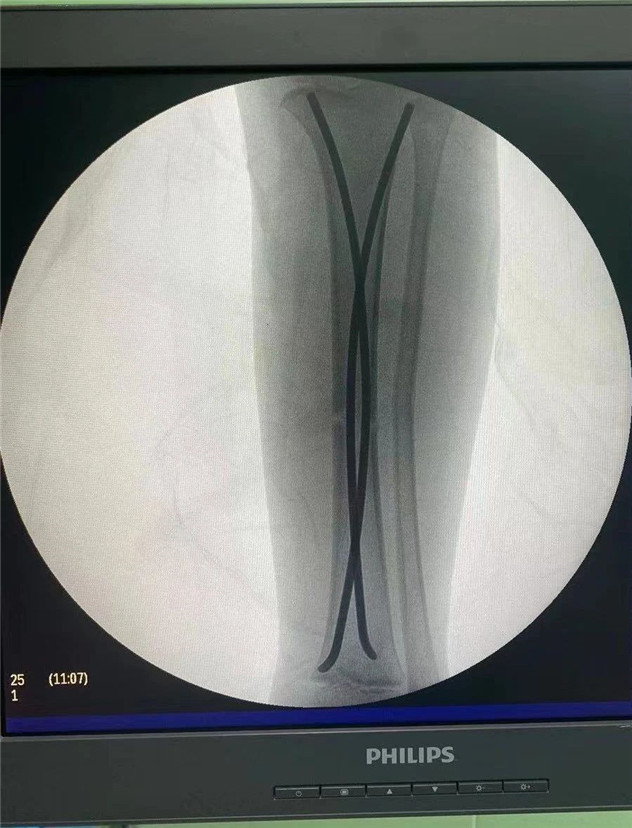

術(shù)中

2020年10月5日,在完成術(shù)前檢查后,睿睿接受了閉合復(fù)位彈性釘內(nèi)固定術(shù),手術(shù)由羅軍主任主刀。術(shù)中只需要兩個(gè)1厘米的小切口,精準(zhǔn)微創(chuàng),僅一個(gè)小時(shí),手術(shù)便圓滿完成。

在接下來的康復(fù)過程中,睿睿非常配合,恢復(fù)的非常好。今年4月12日,睿睿拆除了左腿里的彈性釘。

拆前拆后對(duì)比